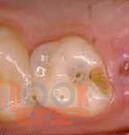

В учебно-методическом пособии рассматриваются основные принципы и методы эндодонтического лечения пульпитов и периодонтитов в детской стоматологической практике. Материал базируется на имеющихся в отечественной и зарубежной литературе современных представлениях по данной проблеме. Издание рекомендуется для использования в основных образовательных профессиональных программах слушателей системы последипломного образования и практической деятельности врачей-стоматологов, клинических ординаторов, аспирантов.